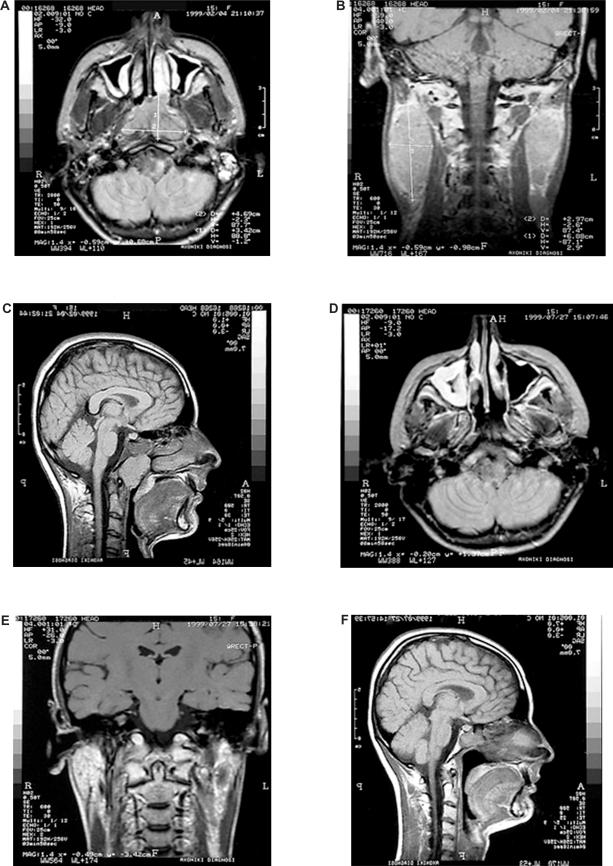

We describe the long-term complications six years after chemoradiotherapy in a 20-year old woman with nasopharyngeal carcinoma. We wanted to know whether the radiation dose was constant throughout the oral cavity, and thus uniformly affecting the corresponding dental and skeletal structures. Clinical and radiologic findings are described six years after chemoradiotherapy based on a two-dimensional computerized treatment planning system. This revealed radiation caries limited only to posterior teeth, proximal caries in the anterior teeth, limited but continuous salivary flow, mild periodontal infection, mild xerostomia, and a regenerative capacity of bones and the developmental process. The quantitative assessment of radiation delivered to the mandible revealed a high radiation dose in the posterior area and a minimal dose in the anterior area. This explains the differences in caries manifestation between the anterior and posterior teeth. According to the present study, individualized radiation fields, using a two-dimensional treatment planning system, result in restriction of severe damage of the dental and skeletal structures, which usually follows chemoradiotherapy. Orthodontic treatment could be initiated according to individual patient needs.

我们描述了一位 20 岁女性鼻咽癌患者在接受放化疗 6 年后的长期并发症。我们想知道口腔内的辐射剂量是否保持恒定,从而均匀地影响相应的牙齿和骨骼结构。根据二维计算机治疗计划系统,在放化疗 6 年后描述了临床和影像学发现。结果显示,放射性龋齿仅限于后牙,前牙邻面龋,唾液流量有限但连续,轻度牙周感染,轻度口干,以及骨骼和发育过程的再生能力。对下颌骨接受的辐射剂量进行定量评估,发现后牙区的辐射剂量较高,前牙区的辐射剂量较低。这解释了前牙和后牙龋齿表现的差异。根据本研究,使用二维治疗计划系统的个体化放射野可限制通常由放化疗引起的牙齿和骨骼结构的严重损伤。可根据患者个体需求启动正畸治疗。